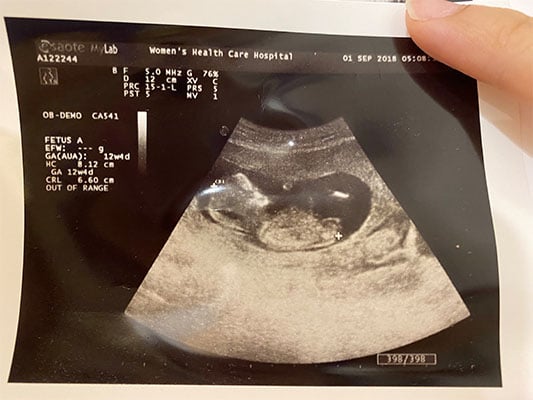

超音波照片保存常見錯誤與避免事項如下:

超音波照片多為熱感紙列印,熱感紙遇熱會變黑且容易褪色,護貝時若遇熱反而加速照片變質,因此不建議直接用護貝機護貝。 -

熱感紙對熱、濕度及揮發性液體(如酒精、清潔劑)非常敏感,這些環境會使照片褪色或模糊。 -

光線會加速熱感紙褪色,應儲存在陰暗處。

拍照或掃描保存電子檔

使用手機拍照或掃描器掃描超音波照片,將電子檔保存於電腦或雲端,避免實體照片褪色。 -

所以,超音波照片因多為熱感紙材質,容易因熱、光、濕度及油脂等因素褪色模糊,最佳保存方式是數位化(拍照或掃描)並妥善備份,實體保存則需避免護貝加熱、避免直接接觸及放置於陰涼乾燥處。